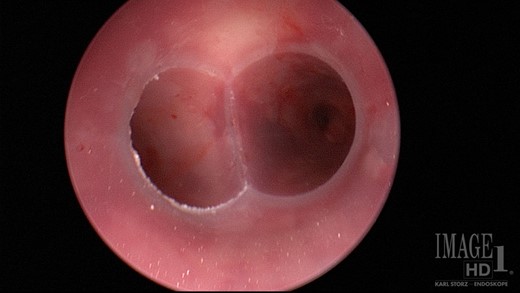

One-year after her original presentation, the patient presented to the emergency room with worsening cough and choking with oral intake. A CT scan of chest revealed a fistula between the right mainstem bronchus and esophagus (Fig. 2A). The patient underwent rigid bronchoscopy revealing a 2-cm defect on the medial wall of the right mainstem bronchus, ~1-cm from the main carina (Fig. 2B). A CT esophagram confirmed extravasation of oral contrast into the tracheobronchial tree (Fig. 3).

(A) CT scan revealing fistula between the right mainstem bronchus and esophagus. (B) Endobronchial view visualizing right mainstem defect.